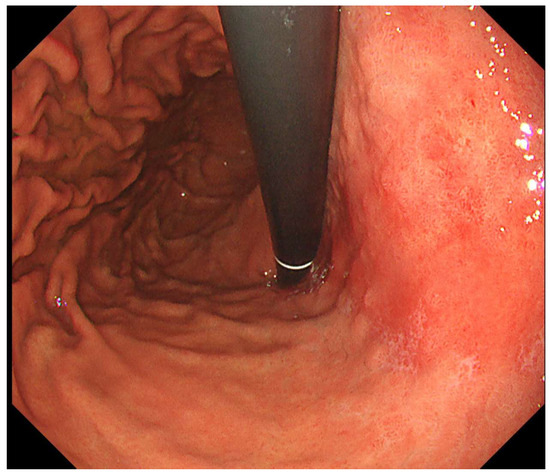

Notably, AI has demonstrated considerable promise in improving the early detection of Barrett’s neoplasia and colonic precancerous lesions. Similarly, the expanding role of endoscopic ultrasound (EUS) is redefining the management of malignant obstructions, offering both diagnostic precision and therapeutic utility. Innovations in small bowel capsule endoscopy have contributed to reduced reading times while maintaining strong diagnostic performance. Furthermore, bariatric endoscopy is emerging as a minimally invasive and effective strategy in weight management, with important clinical implications.

This Special Issue, "Advances in Gastrointestinal Endoscopy: From Diagnosis to Therapy", will showcase cutting-edge developments across the endoscopic spectrum, from foundational techniques in gastroscopy and colonoscopy to advanced procedures including ERCP, therapeutic EUS, AI-enhanced imaging, and bariatric endoscopic interventions.